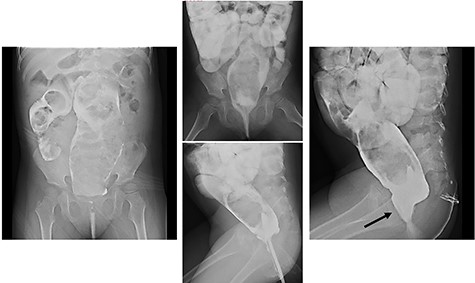

We report herein a case of a 4-year-old girl with ultrashort-segment HD (USHD). She was born at 29 weeks gestation from a twin pregnancy. Her birth weight was 1013 g. After birth, she was administered glycerin enemas to facilitate defecation. Thereafter, she was medicated with sodium picosulfate hydrate for chronic constipation, but she passed stool once in 4–5 days. When she was 4 years old, she was medicated with polyethylene glycol electrolyte solution (MOVICOL® [macrogol 4000]; EA Pharma Co., Ltd, Tokyo, Japan) in another hospital for chronic constipation. After she drank the MOVICOL® twice, her abdomen distended rapidly without passing stool, and she was transported to a hospital. An abdominal X-ray showed a stored stool mass (Fig. 1). A barium enema study revealed dilatation from the rectum to the sigmoid colon due to the stool mass and the rectum was smooth with funnel-shaped tapering toward the anus when she forced herself to defecate (Fig. 2). USHD was suspected, so she underwent anorectal manometry, which showed negative normal reflux. A surgical rectal full-thickness biopsy was performed 2 cm proximal to the dentate line under general anesthesia, which revealed very few ganglion cells in Auerbach’s plexus (Fig. 3a–c). She was suspected to have HD and underwent a Soave endorectal pull-through with an oblique anastomosis, where the pulled-through bowel was anastomosed posteriorly 0.5 cm from the dentate line, laterally 1.0 cm from the dentate line and anteriorly 1.5 cm above this point (Fig. 4). The posterior wall of the aganglionic anorectum was split longitudinally to the level of the dentate line. The resected specimen showed sparse ganglion cells with small cytoplasm in Auerbach’s plexus of the mucosectomy in the rectum (Fig. 5 ①, a and b). In the sigmoid colon of the resected specimen, most of the ganglion cells had scanty cytoplasm, whereas occasional ganglion cells with abundant cytoplasm were visualized (Fig. 5 ②, c and d). She passed stool 4–10 times a day for 6 months postoperatively, but the frequency of passing stool gradually deceased to once or twice a day without anastomotic strictures. Defecation was controlled without medications for 12 months postoperatively.

Barium enema: barium enema revealed dilatation from the rectum to the sigmoid colon due to a stool mass and the rectum showed a smooth funnel-shaped tapering toward the anus when she forced herself to defecate (black arrow: funnel-shaped tapering).